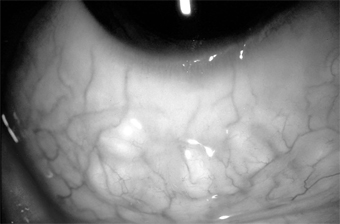

Lymphangiectasis is characterized by localized small, clear, tortuous dilations in the conjunctiva. They are merely dilated lymph vessels, and no treatment is indicated unless they are irritating or cosmetically objectionable. They can then be cauterized or excised (Figure 5-23).

Figure 5-23

Figure 5-23: Conjunctival lymphangiectasis. Note the clear tortuous dilations in the conjunctiva.